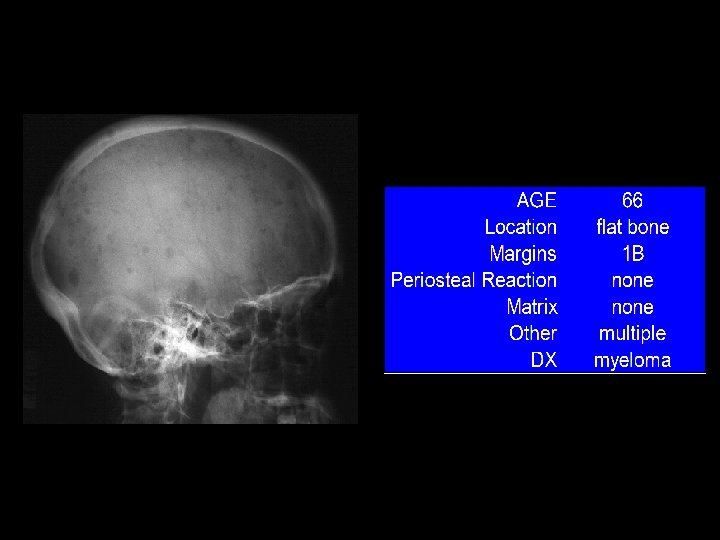

In case of Bone Tumors: look for Location! Age Age Behavior

Location and age of patient most important • parameters in classifying a primary bone tumor. Simple to determine from plain • radiographs.

Reaction of bone to tumor Limited responses of bone • destruction: lysis (lucency) reaction: sclerosis remodeling: periosteal reaction Rate of growth determines bone • response slow progression, sclerosis prevails – rapid progression, destruction prevails –